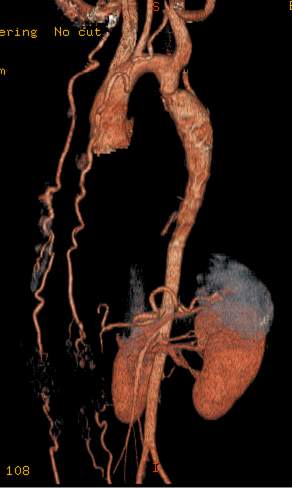

8.2.2.4. Aneurysm disease

Aneurysms are defined as dilatations of the vessels that are 50% wider than the normal arterial diameter. In a true aneurysm, the dilated segment’s wall contains all the layers of the normal arterial wall, in contrary to false- or pseudoaneurysms, which are also segmental dilatations of the arterial lumen, but their wall contains only in part all the layers of a normal arterial vessel; they are caused by a certain local effect (e.g.: trauma, iatrogenic injury, etc.).

Large vessel dilatations can cause signs of compression, depending on its localization. The circulation slows down within the expanded vessel and a consequent thrombogenic process occurs along the luminal wall, often reaching such a high grade that the permeable lumen barely shows any dilatation. The thrombus can act as a source of distal embolization and can cause acute ischemic signs when reaching certain arterial territories. Finally, the most important complication of the progressively expanding aneurysm is rupture, which causes circulatory insufficiency and presents as a high mortality condition, leading to patient death within a few hours without an interventional procedure. The risk of rupture increases exponentially with the size of the diameter.

The role of imaging aneurysms, on one hand, is to provide precise measurements about its size, especially about its greatest diameter, on the other hand, to follow-up the patients. An aortic aneurysm with a diameter above 6 cm is considered at a high risk for a rupture and requires interventional procedure. Dilatations over 5 cm require a close monitoring to be able to detect any further increase in size in time. Aneurysms of a size smaller than 5 cm require imaging follow-up at every 6 months or once a year if their size does not change. Beside the precise measurements, the role of imaging is also to characterize the appearance of the lesion in order to select ones that require surgical reconstruction and ones that are suitable for endovascular intervention. The anatomic characteristics that should be assessed at each imaging examination are: the location of the proximal and distal neck of the aneurysm, the relation of the origin of the side branches, wall thickness, the thickness of the mural thrombus and finally to detect signs in the perivascular tissues that are suggestive of an impending rupture.

Ultrasound examination is a reliable screening tool and is also useful for patient follow-up. However, the reproducibility of the diameter measurements of an irregularly shaped vessel is considered limited. Contrast enhanced US can increase the diagnostic sensitivity for such hardly depictable lesions. CT and MRI are able to assess well aneurysms regardless of their location and size. They provide the highest visibility for primary diagnostics and planning of surgical interventions. Intrathoracic and intracranial aneurysms can only be followed up with these techniques since US examination has limited ability in these regions. In case of scheduled examinations MRI is the preferred method, if available, since it does not come with harmful radiation which would accumulate in a constantly controlled patient. In cases when rupture is suspected CT is the method of choice due to its higher availability in emergency and shorter examination time

Image

A non-ruptured (stable) aneurysm with an extended mural thrombus

Ruptured aneurysm with retroperitoneal hematoma

Fig. 24., 25.: Abdominal aorta aneurysm, CT angiography